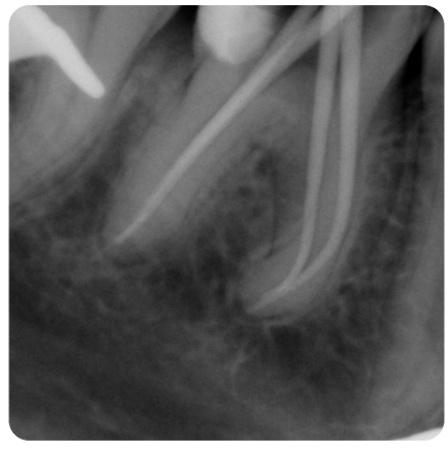

Podczas gdy w dolnym łuku dr Michał Mokijewski przeprowadzał zabiegi regeneracyjne i implantacje, zajęłyśmy się leczeniem łuku górnego.

Zgodnie z zasadą, że prace protetyczne powinny być oparte na zdrowych i solidnych fundamentach, zaczęłyśmy od podstaw – wymiana nieszczelnych wypełnień, powtórne leczenia kanałowe.

Praca została zwieńczona odbudową zębów koronami cyrkonowymi. Brakujący ząb, którego nie można było uzupełnić implantem z powodu za małej ilości miejsca, odtworzono za pomocą cyrkonowego mostu.